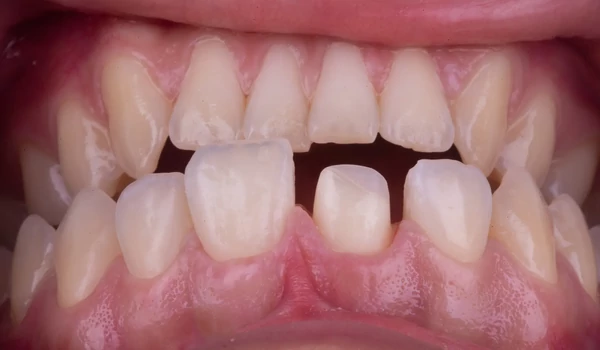

BevezetésA frontfogak traumás törései egyaránt megkövetelik az esztétikum és funkció tökéletes egyensúlyát – mindezt gyakran a páciens érzelmi nyomása alatt. Dr. Koray Kendir esetbemutatója azt szemlélteti, hogyan lehet egy korábban nem megfelelően kezelt centrális metszőt biomimetikus (a természetre emlékeztető) megközelítéssel és Kuraray Noritake termékek segítségével sikeresen rehabilitálni kuraraynoritake.eu. Az eset összefoglalásaEgy 23 éves nőbeteg jelentkezett egy hónappal a trauma után. A sérült 11-es fogon (FDI jelölés) korábban más szakorvos által végzett gyökérkezelést és direkt kompozit felépítést találtak, amely azonban esztétikailag és marginálisan is elégtelennek bizonyult (1. ábra) kuraraynoritake.eu. |

1. ábra. Klinikai helyzet kiinduló pont |